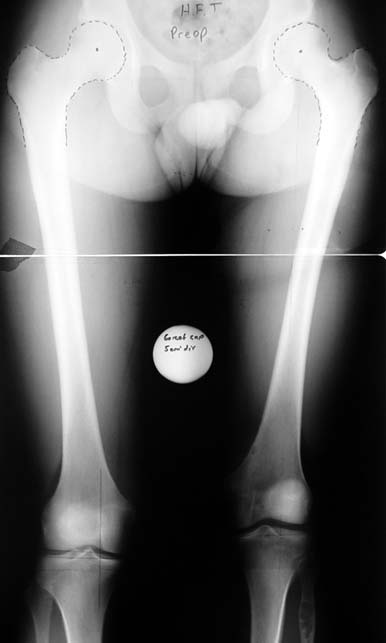

3- POSTTRAVMATİK BACAK KISALIĞI (YANLIŞ KAYNAMA)

Bu Bacak Kısalık tipi bir kırığın kısalmış pozisyonda kaynaması ile oluşur. Bir çok vaka yetişkinlerde görülür ve sadece bir uzatma ile tedavi edilebilir. Ek deformiteler de aynı anda düzeltilebilir. Bu hastaların çoğu çivi üzerinden uzatma veya tam implante edilen çivi ile tedavi edilebilirler.